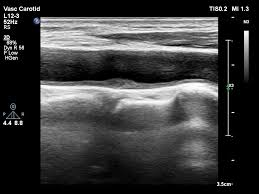

- 젤을 바른 후 초음파 탐촉자를 경동맥 위에 대고 영상 관찰

- 혈류 속도 측정과 플라크 유무 확인

검사 결과에서 주로 보는 지표

판독 시 중요한 평가 항목은 다음과 같습니다.

- IMT 수치(혈관 노화 및 동맥경화 지수)

- 혈류 속도 증가 여부